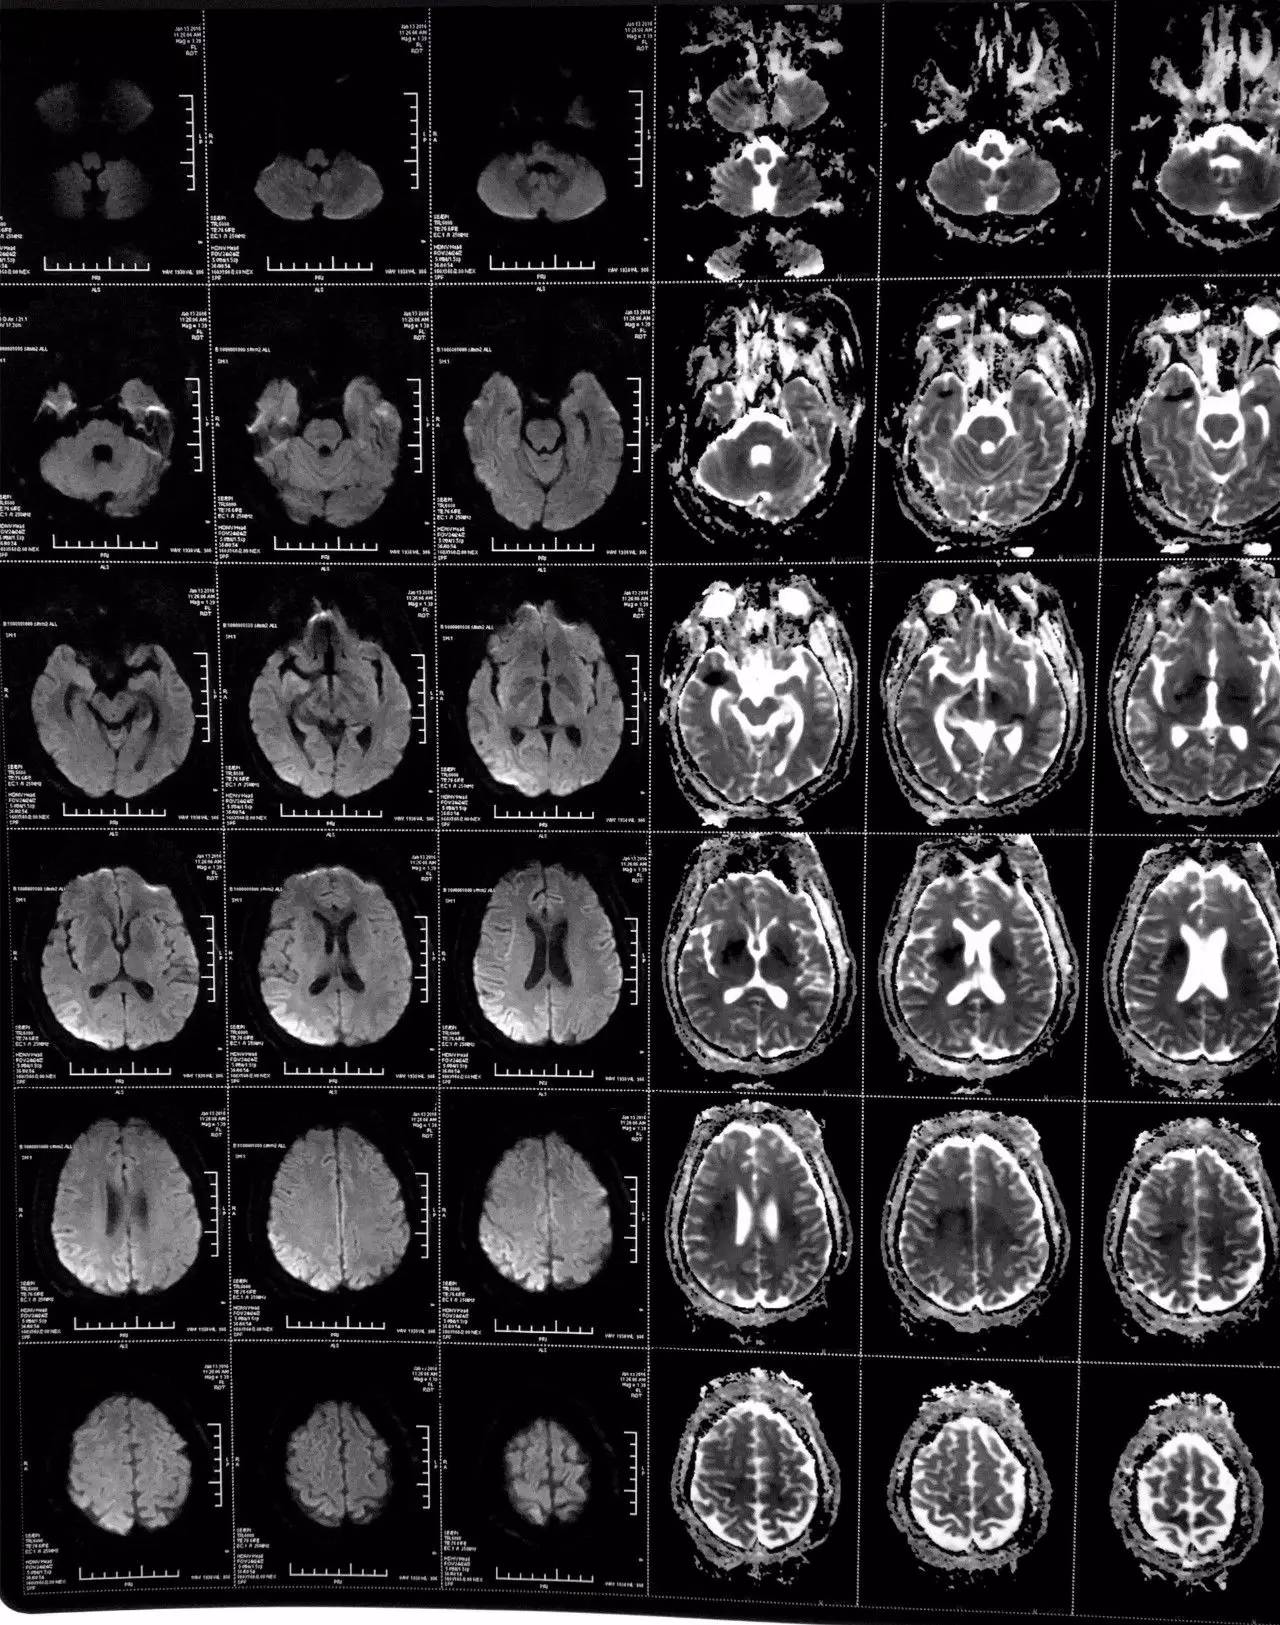

▼患者影像资料